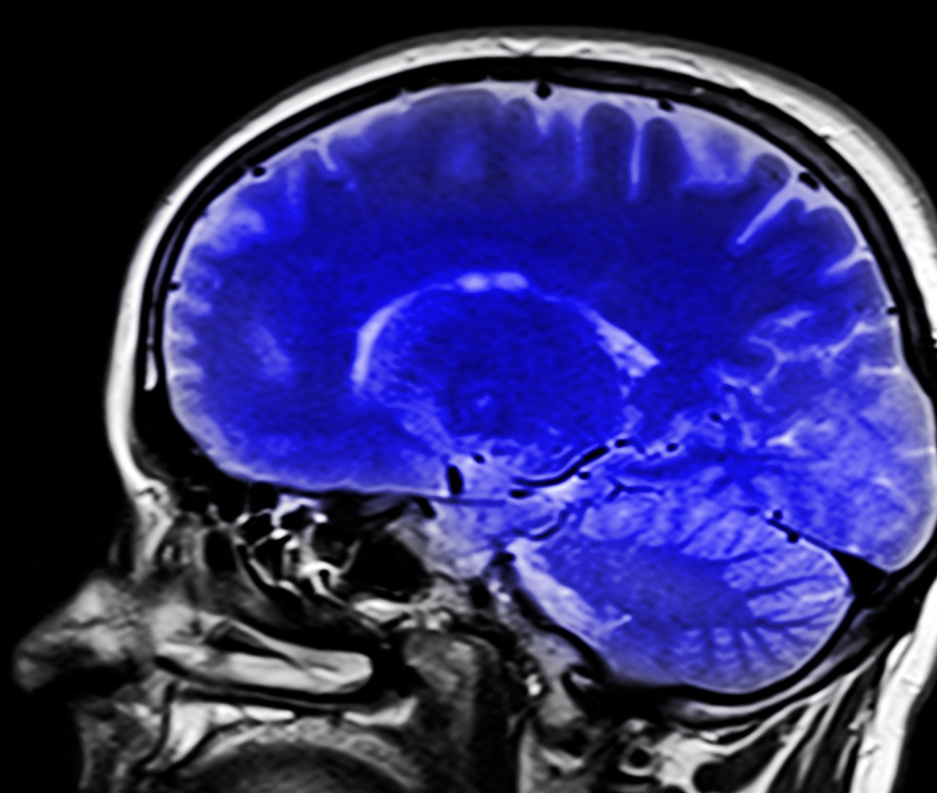

Глиобластома, один из самых агрессивных видов рака мозга, использует глюкозу не так, как здоровые клетки, что способствует её быстрому росту.

Согласно исследованию, опубликованному в журнале Nature, опухоль перенастраивает сахарный обмен и превращает глюкозу не в энергию, как это делают обычные клетки, а в строительные блоки для ДНК и РНК. Это позволяет раковым клеткам быстрее делиться и распространяться по организму.